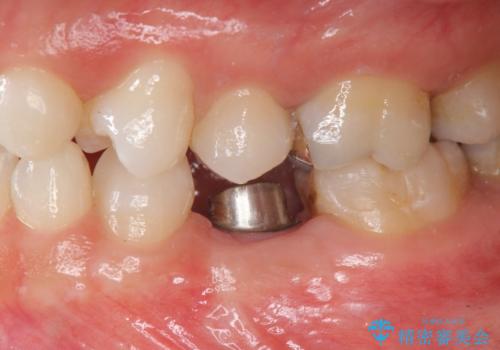

歯根が吸収し残すことのできない乳歯を抜去後、隣の歯を削らずに済むインプラント治療で咬合機能の回復を計画します。

- 44万円(インプラント・チタンカスタムアバットメント・ジルコニアクラウン・仮歯)費用は治療当時の料金となります

乳歯の抜去後、インプラントを用いてしっかりと咬合機能を回復することができました。